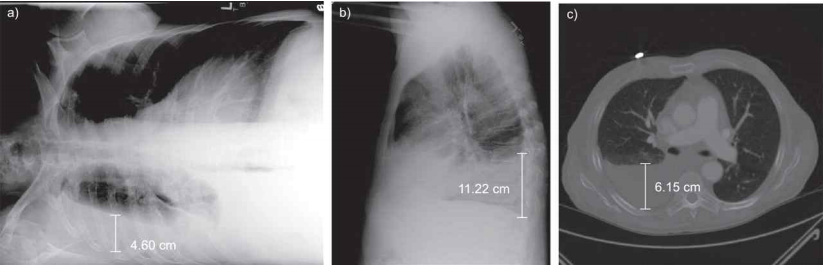

흉막 삼출액(pleural effusion)과 같은 합병증은 흉부 방사선 사진에서도 발견될 수 있다. 측면 흉부 방사선 사진(*chest decubitus)은 폐 경화 및 흉막 삼출액의 진단 정확도를 높일 수 있다.

2) Chest CT

흉부 전산화 촬영(computed tomography, CT) 검사는 폐실질 이상 소견을 평가하는 데 있어서 가장 정확한 검사로, 흉부 X선 검사에서 이상소견이 없는 경우에도 폐렴에 합당한 영상 소견을 보일 수 있다. 또한, 늑막염 및 폐실질 괴사와 같은 폐렴 합병증의 진단, 무기폐, 폐경색, 종양, 간질성 폐질환 등과 같이 폐렴과 유사한 X선 소견을 보일 수 있는 다양한 비감염성 폐질환의 배제 및 감별진단에 있어서 흉부 X선 보다 더욱 정확하다.

다만 흉부 X선 검사에 비해서 높은 가격과 방사선 조사에 따른 위험성 등을 감안했을 때, 폐렴 환자에서 CT 검사는 폐색전증 등 다른 동반 가능한 질환에 대해 감별이 필요한 경우, 진균성 감염이 의심되는 경우, 다른 기저 폐질환 등으로 인해서 흉부 X선에서 폐 침윤 여부를 확인하기 어려운 경우, 폐렴 치료에 잘 반응하지 않아서 폐렴의 합병증을 확인하기 위한 경우 등 특수한 상황에서 선택적으로 시행이 고려될 수 있다.